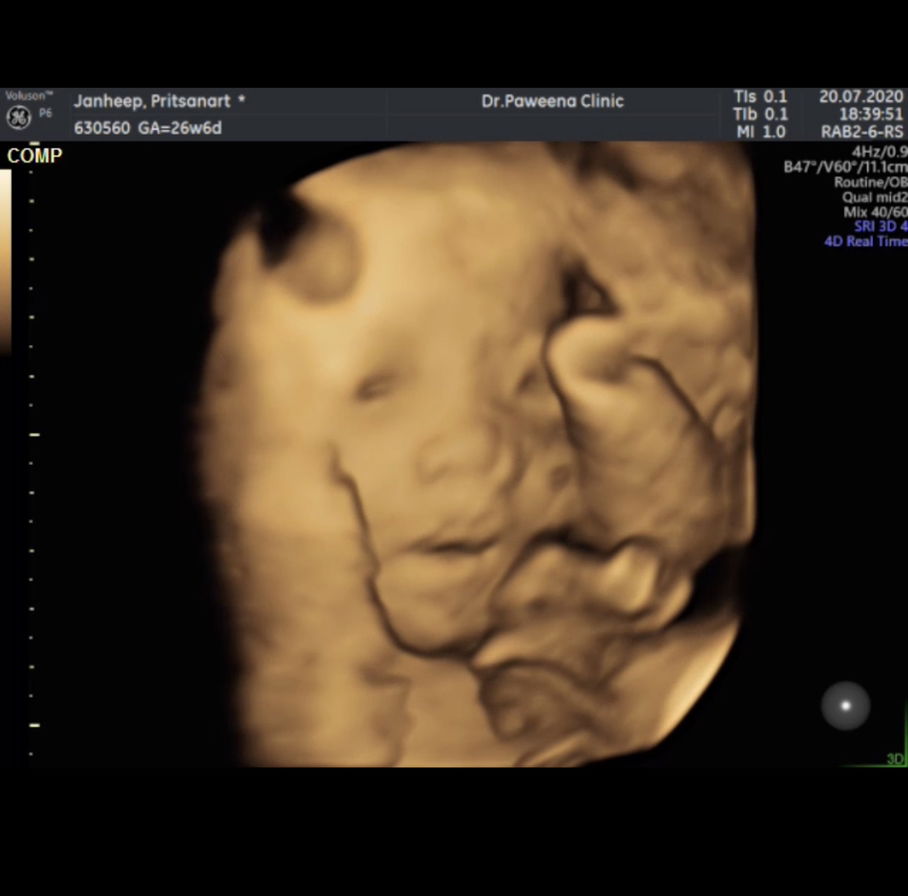

#ใช่น้องลืมตามั้ยค่ะแม่ๆ??? ซาวด์ตอน27วีค👶🏻 ตอนซาวด์น้องดิ้นมากๆไม่อยู่เฉยเลยค่ะเลยจับภาพยาก

น่าจะลืมตาค่ะแม่